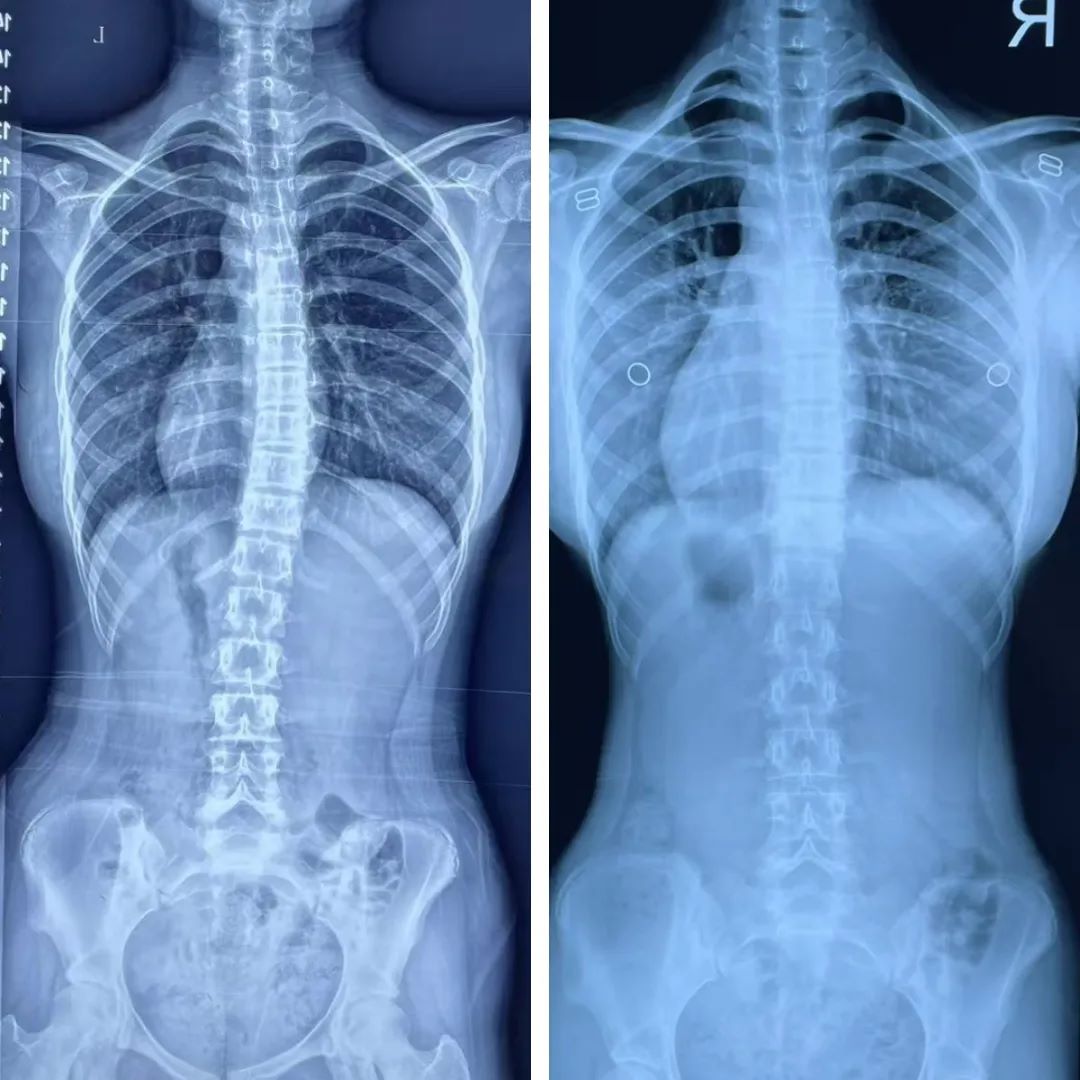

▲治疗前后对比

经过四个月坚持不懈的努力,丽丽再次来到河南大学第一附属医院进行复查。当DR影像显示脊柱侧弯已经恢复正常时,丽丽和家长激动得热泪盈眶,曾经那个有些自卑的少女,如今脸上洋溢着自信的笑容……